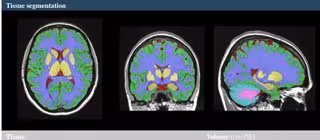

Vol2Brain es capaz de analizar hasta 135 regiones del cerebro, a partir de imágenes de Resonancia Magnética (RM) del cerebro. Ofrece DATOS sobre los volúmenes de los tejidos de la cavidad intracraneal (ICC), así como de algunas áreas macroscópicas como los hemisferios cerebrales, el cerebelo y el tronco cerebral. Además, proporciona también los volúmenes e índices de asimetría de estructuras corticales y subcorticales, de gran importancia en el ámbito neurológico, así como medidas de grosor cortical.

"El usuario solo ha de enviar un fichero comprimido a través de la web y en 20 minutos recibirá un correo con los resultados de la segmentación y procesado de los volúmenes cerebrales. Los sistemas similares actuales tardan una media de 6 horas en ofrecer esta información", declara José Vicente Manjón.